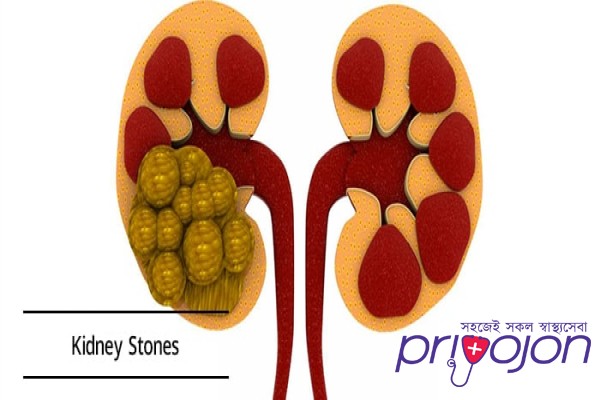

Kidney stone disease, also known as urolithiasis, is when a solid piece of material (kidney stone) develops in the urinary tract.[2] Kidney stones typically form in the kidney and leave the body in the urine stream.[2] A small stone may pass without causing symptoms.[2] If a stone grows to more than 5 millimeters (0.2 in), it can cause blockage of the ureter, resulting in severe pain in the lower back or abdomen.[2][7] A stone may also result in

A urinary calculus may be a crystalline and hard mineral material that gets formed within the kidney or in our tract . Kidney stones are a standard explanation for hematuria (blood in urine) and sometimes cause severe pain within the abdomen, groin or within the flank. Kidney stones also are called renal calculi. Urinary stones, mostly develop in patients who are betw